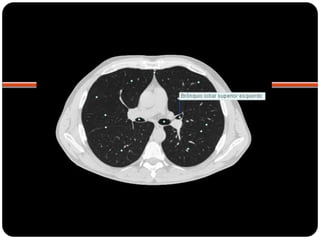

 TC janela de parênquima

BPD: BLSD

BI - BLM

BI – BLID

BPE: BLSE

BLIE